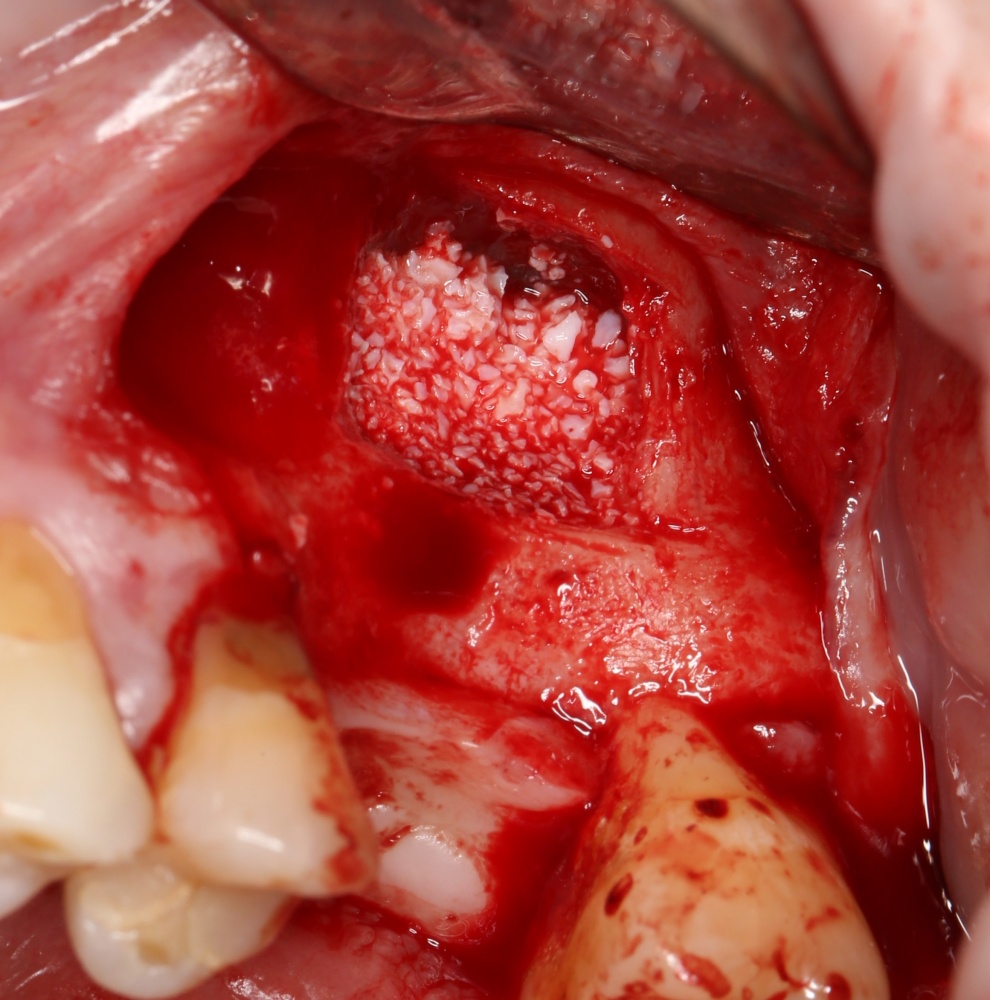

Кстати, обрати внимание на ширину альвеолярного гребня (левая картинка). Она чуть меньше 3 мм. Это объясняет, почему я засомневался в возможности установки имплантатов одновременно с остеопластикой. Понятно и без КЛКТ.

Наперво, мне нужно удалить разрушенный зуб и получить костный аутотрансплантат.

Для получения костного блока, мы открываем донорскую зону, наружную косую линию нижней челюсти.

Возвращаемся к основной операционной области. Еще раз посмотрим на альвеолярный гребень, поофигеваем от его ширины и моих грандиозных планов: